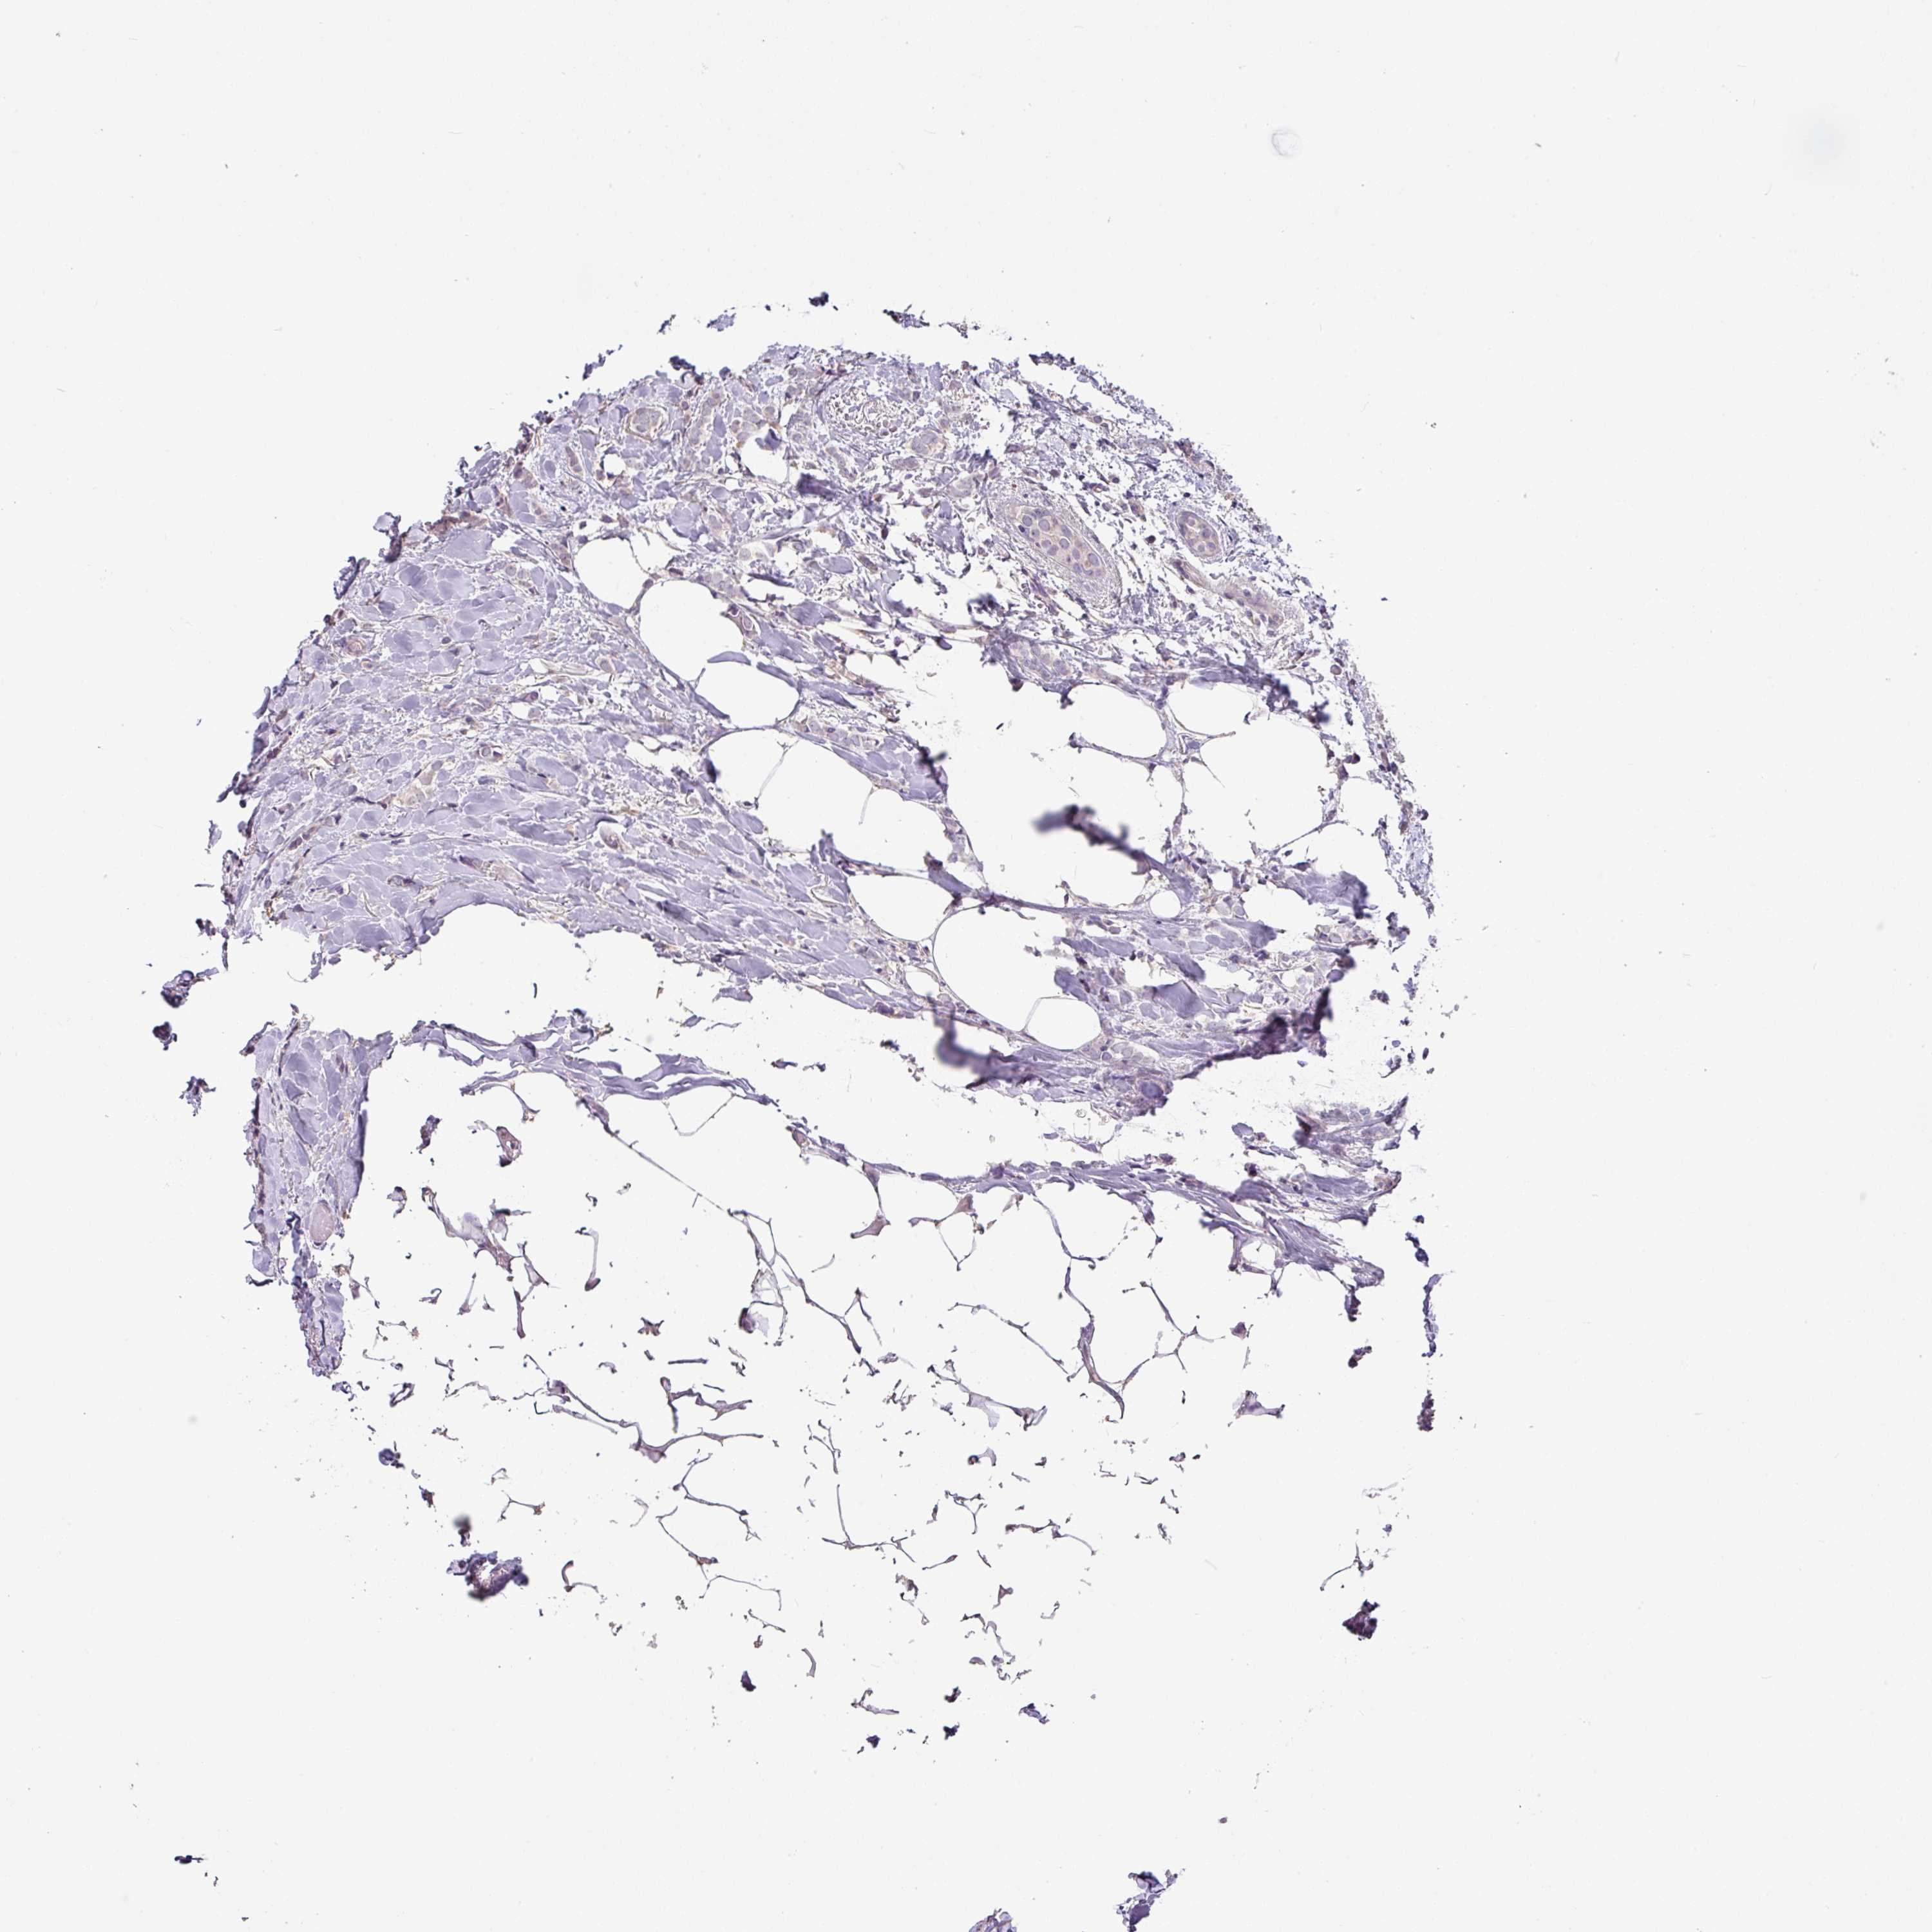

BRCA TCGA BRCA VALIDATION PROTEIN EXPRESSION